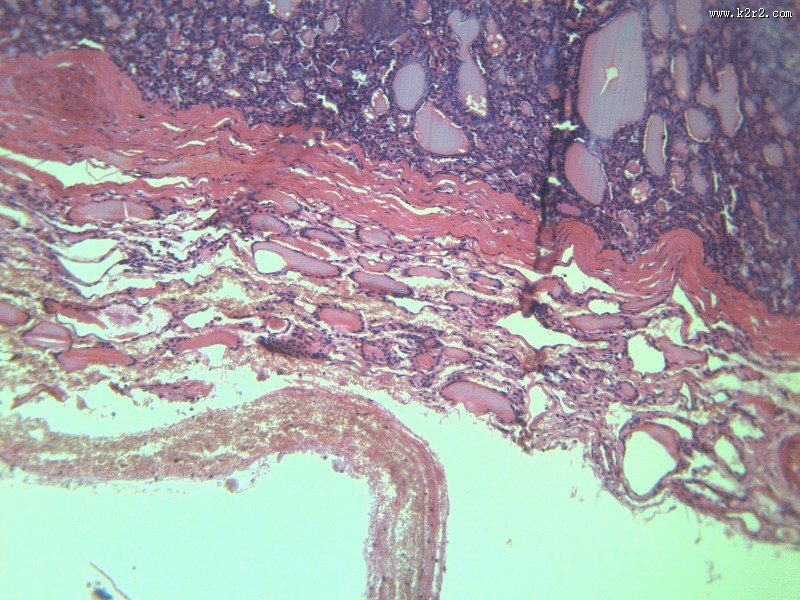

甲状腺瘤 - 第10张 共有

医学

显微切片

肿瘤

thyroidadenoma

甲状腺瘤

腺瘤